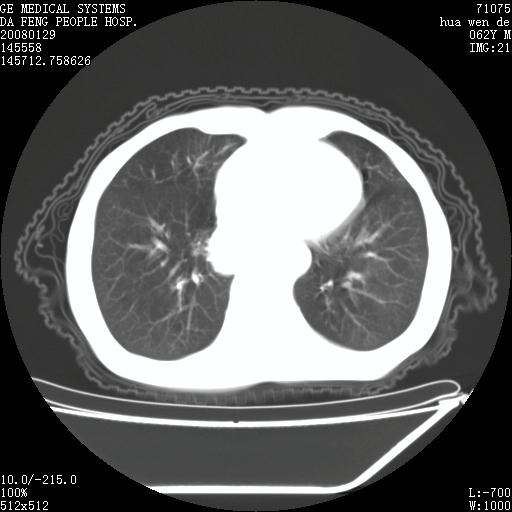

男性,67岁。作肺部检查时发现

理由:1、右上肺内病灶,空洞形成,有液平。

2、肺内多处炎症。

3、前段肺内炎症,支气管引流通畅,与肿块无关系。

1.整个食管扩张,未见明显占位性病变,贲门区亦未见明显占位病变,考虑:贲门失驰缓症;

2.右上肺病变边缘可见毛刺,囊壁厚度不均匀,周围境界较清楚,未见炎性渗出性影,右上肺外带可见片状影,边缘不清,考虑:肺癌伴空洞形成、右上肺炎。

食管全程扩张,壁均匀不厚,喷门失弛缓症

右上肺空洞可见液平,临近肺野磨玻璃密度,考虑1.结核2.脓肿